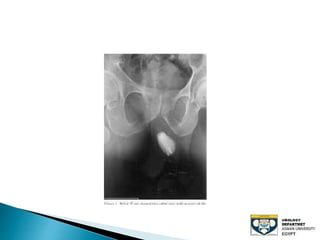

The document discusses urinary tract stones, detailing their types, causes, symptoms, and diagnostic methods. It highlights the risk factors such as infections and obstructions, with men being more commonly affected. Treatment options include various surgical methods, particularly for managing bladder outflow obstruction and lithiasis.